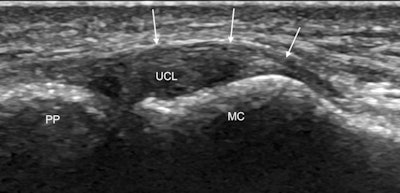

Spotting the concavity seen on the metacarpal head, between the metacarpal tubercle and the articular surface, is key to identifying the normal ulnar collateral ligament and confirms that the transducer is correctly oriented at the ligament attachment. The ulnar collateral ligament should appear as an echogenic fibrillar band bridging the MCP joint. The deeper fibers are predisposed to anisotropy, and this should not be confused with a partial thickness tear, McCarthy stated.

The next structure to look for is the adductor aponeurosis, which can be seen as a thin curvilinear echogenic structure overlying the ulnar collateral ligament. It may be difficult to identify the adductor aponeurosis in the static position so she advocates the use of dynamic imaging with flexion and extension of the interphalangeal joint to move the aponeurosis which will then be seen as a thin echogenic band gliding over the ulnar collateral ligament.

Tear identification

In an undisplaced tear in which the ligament looks thickened and hypoechoic often with a cleft extending through it, there is no significant proximal retraction, so the ligament appears symmetrically centered over the MCP joint. Dynamic imaging once again using joint extension and flexion will show the aponeurosis gliding over the thickened hypoechoic torn ligament. Meanwhile, in Stener lesions the torn ligament retracts proximal to the MCP joint to lie adjacent to the metacarpal head. The ligament has an asymmetrical appearance with a larger retracted proximal end, which looks like a round hypoechoic mass.